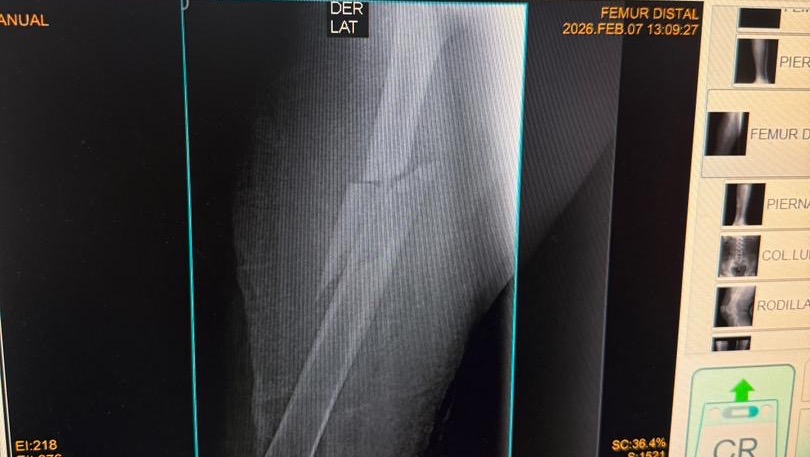

A sus 27 años, Jean Manuel Colella estaba cumpliendo una de sus metas más grandes: realizar sus prácticas universitarias en Barquisimeto, Venezuela. Sin embargo, la madrugada del 07 de febrero, su vida cambió en un segundo. Fue víctima de un terrible accidente automovilístico donde, lamentablemente, los responsables se dieron a la fuga, dejándolo atrás con heridas graves. Hoy, Jean Manuel enfrenta el reto más difícil de su vida. El accidente le causó múltiples fracturas en ambas piernas, siendo su pie derecho el más afectado. Para que él pueda volver a caminar, trabajar y terminar su carrera, necesita una cirugía de reconstrucción urgente. Cada granito de arena cuenta. Tu donación, por pequeña que parezca, es un paso más cerca de devolverle la movilidad a un joven que tiene todo un futuro por delante. ¡Ayúdanos a que Jean Manuel vuelva a ponerse de pie!

At the age of 27, Jean Manuel Colella was achieving one of his biggest goals: completing his university internship in Barquisimeto, Venezuela. However, in the early hours of February 7th, his life changed in an instant. He was the victim of a horrific car accident where, heartlessly, those responsible fled the scene, leaving him behind with severe injuries. Today, Jean Manuel faces the toughest challenge of his life. The accident caused multiple fractures in both legs, with his right foot being the most severely affected. In order for him to walk again, work, and finish his degree, he needs urgent reconstructive surgery. Every little bit helps. Your donation, no matter how small it may seem, is one step closer to restoring mobility to a young man with his whole future ahead of him. Help us get Jean Manuel back on his feet!